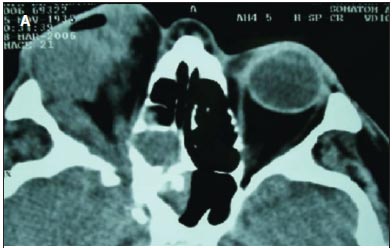

Regarding the malignant neoplasias (seven patients, 58.3%), there were four cases of adenoid cystic carcinoma. The mean age of the patients with adenoid cystic carcinoma was 51 years-old (range, 26 to 65 years-old). Two patients presented a painful palpable mass of rapid growth, proptosis and inferomedial displacement of the globe, and two presented reduced visual acuity, choroidal folds, restricted ocular motility and swelling. Two patients were treated with lateral orbitotomy with resection of the tumor and postoperative radiation, and two were treated with orbital exenteration and postoperative radiation. In these patients, the orbital exenteration and the postoperative radiation were chosen because the preoperative axial and coronal computed tomography showed diffuse orbital involvement, including extraocular muscles and optic nerve. Macroscopically, the tumor was rounded and irregular (Figure 1B). Histologically, two cases were of cribriform pattern (Figure 2C), and two were of solid growth pattern (Figure 2D). One case with cribriform pattern and two cases with solid growth pattern showed necrosis and perineural invasion. The other case with cribriform pattern presented no necrosis and perineural invasion. According to the UICC/TNM Classification, the two cases of cribriform pattern were classified as T2N0M0, and the two cases of solid growth pattern were classified as T4N0M0. The mean follow-up period was 6.5 years (range, 4 to 10 years). No tumoral recurrence was observed in two patients (adenoid cystic carcinoma with cribriform pattern). The patients with solid growth pattern and T4N0M0 developed metastasis to the brain and died of the disease.

The first patient with mucoepidermoid carcinoma was a 70 year-old man, and the second was a 58 year-old woman. Both patients presented a painful palpable mass, proptosis, displacement of the globe off axis, swelling, reduced visual acuity and choroidal folds. The first patient had infiltration into the maxillary and the ethmoid sinus (Figures 3A, B and C) and was treated with orbital exenteration, maxillectomy, ethmoidectomy, postoperative radiation and postoperative chemotherapy. The second patient was treated with lateral orbitotomy with complete resection of the tumor and postoperative radiation. Macroscopically, the second patient showed a soft and reddish tumor (Figure 1C). Histologically, both cases were low-grade and composed of epidermoid cells with mucus-filled vacuoles embedded in a mucoid background (Figure 2E). The mean follow-up was 3.5 years (range, 2 to 5 years). According to the UICC/TNM Classification, the first case was classified as T4N1M0, and the second case was classified as T3aN0M0. The first patient developed metastasis to the brain and died of the disease. The second patient presented no evidence of recurrence of the disease five years after the initial surgery.